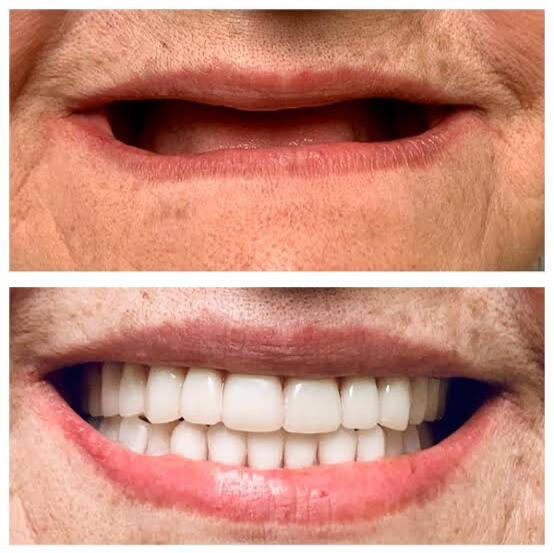

Get the smile you deserve!

At City Dental Clinic, we care about your dental health. Whether it’s a routine check-up or a more complex procedure, you’re in good hands. Start your journey to a healthier smile today!

City Dental Clinic is a premier dental care facility located in Biswanath Charali, Assam. Led by Dr. Narendra Chetri, who brings over 15 years of professional experience, the clinic is committed to providing exceptional dental services tailored to meet a wide range of oral health needs. With a focus on advanced care and a patient-centered approach, Our Clinic offers top-of-the-line treatments designed to ensure lasting smiles and optimal oral health for every patient.

Crafted with Precision